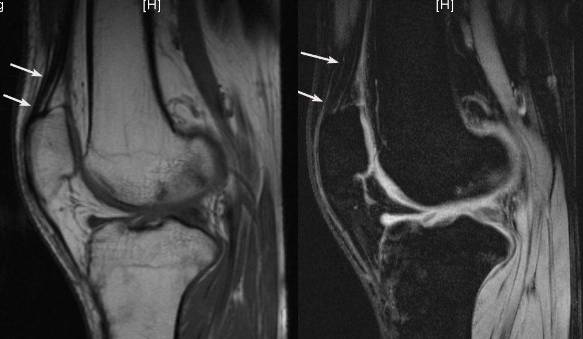

4、桶柄状撕裂

为纵形撕裂伴碎片向内侧移位,这种移位的片段类似于桶的柄,该型撕裂几乎累及半月板的所有部位,常易漏诊,在 MRI 上可以有多种表现,主要为半月板的宽度减小,在通过半月板体部的冠状面上未见到与对侧半月板共同构成的蝶形表现,同时可见到内移的半月板碎片位于髁间窝或交叉韧带旁,可形成双前、后交叉韧带征,这一征象在诊断半月板桶柄状撕裂中有重要意义;